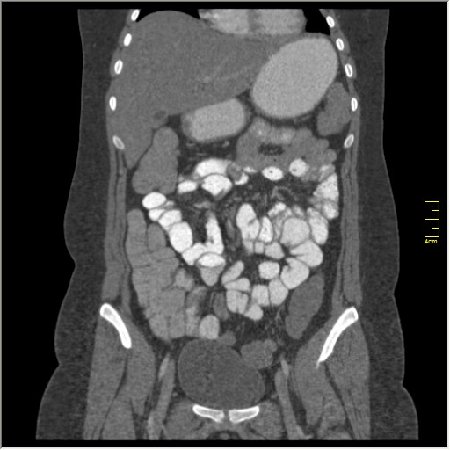

КТ энтерография

Демонстрационные изображение, оцените возможности метода! Толщина среза реконструкции 0.5-1 мм.